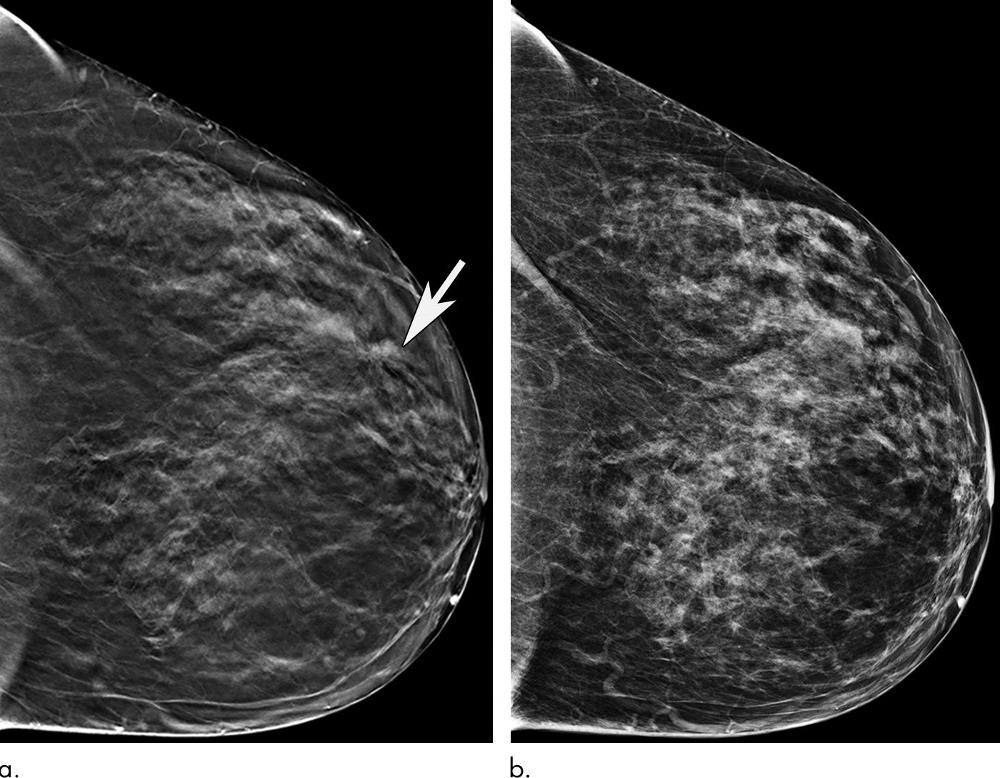

Figure 2. Images in a 72-year-old woman with screening-detected invasive carcinoma. (a) Tomo¬synthesis image from left craniocaudal view demonstrates architectural distortion in lateral aspect of left breast at anterior depth (arrow). (b) Finding is not as well demonstrated on two-dimensional left craniocaudal view. Patient underwent image-guided core biopsy and subsequent lumpectomy, which revealed grade 2 invasive lobular carcinoma.

High-res (TIF) version